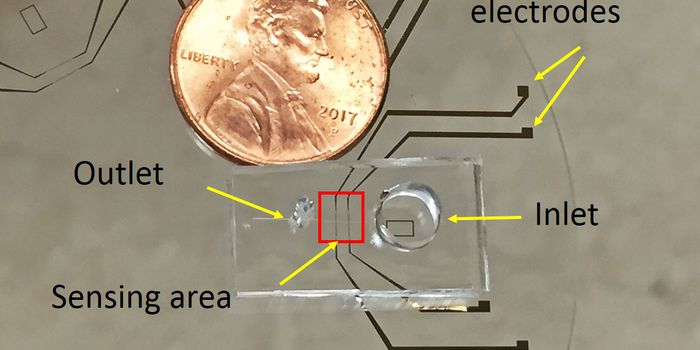

MAY 20, 2021Clinical & Molecular DXForget lab-based tests—a new portable microfluidic device links to a mobile app, diagnosing gonorrhea in just 15 m ...